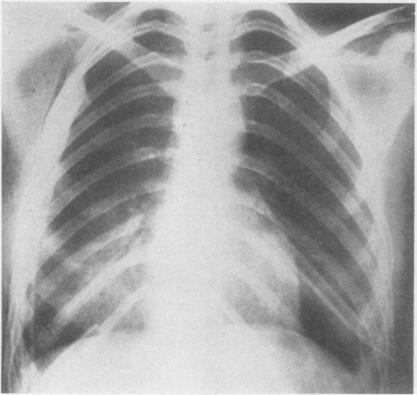

Thorax. 1965 May;20(3):261-9. doi: 10.1136/thx.20.3.261.